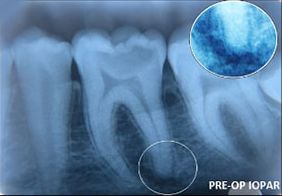

Regenerative Endodontic Procedure -

Naseem Shah -

PRF Mediated REP in 21 with 18 Months Follow Up

Complete Bony Healing, Apex Closed, Lateral Wall Thickening- 15.5%